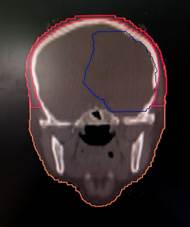

to the level of the foramen magnum (6) as depicted in Figure 1 given below.

Figure 1. shows scalp contours in axial, coronal,

and sagittal planes.